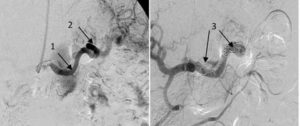

- Селективная ангиография. Методика помогает обнаружить характерные для данного образования тромботические массы;

Метод выбора — эндоваскулярная окклюзия (закрытие просвета) артерии селезенки. Операцию проводят всем больным, у которых аневризма не связана с воспалительными заболеваниями панкреатической железы или желудка. Остальным пациентам выполняются открытые операции:

- Ангиопластика — с помощью искусственного или натурального сосуда выполняется замещение пораженной части артерии, либо делается образный обход, который снижает давление в месте патологических нарушений. Во время операции используется положительный эффект эмболизации селезеночной артерии при её аневризме. Такое решение позволяет избежать необходимости в замене органа.